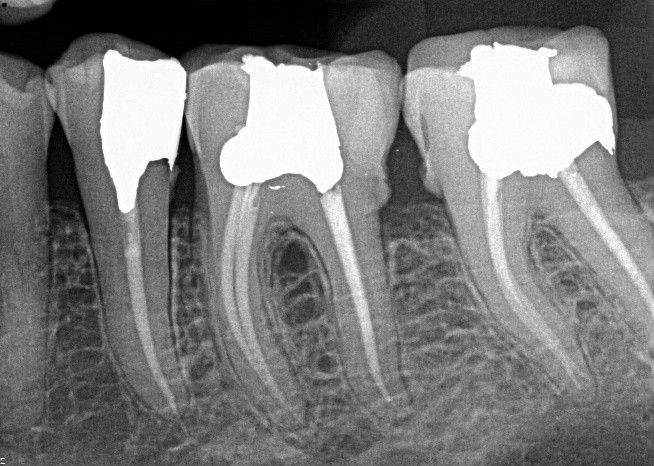

4. (Select ONE OR MORE correct answers)

What observation(s) can be made for tooth 3.6?